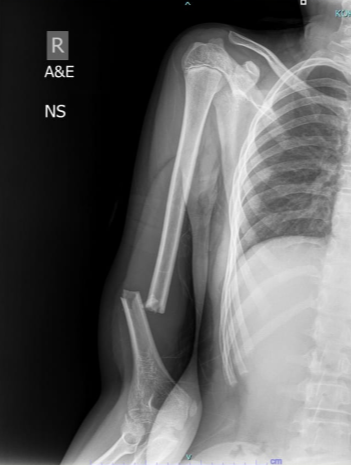

A Novel Approach to Proximal Humerus Giant Cell Tumor: Cement Spacer and Screw Interdigitation for Optimal Stability

Kunal Chaudhari , Rachit Sekhrajka , Mishil Parikh , Vishakha Kurundwade

………………………………p.317-322